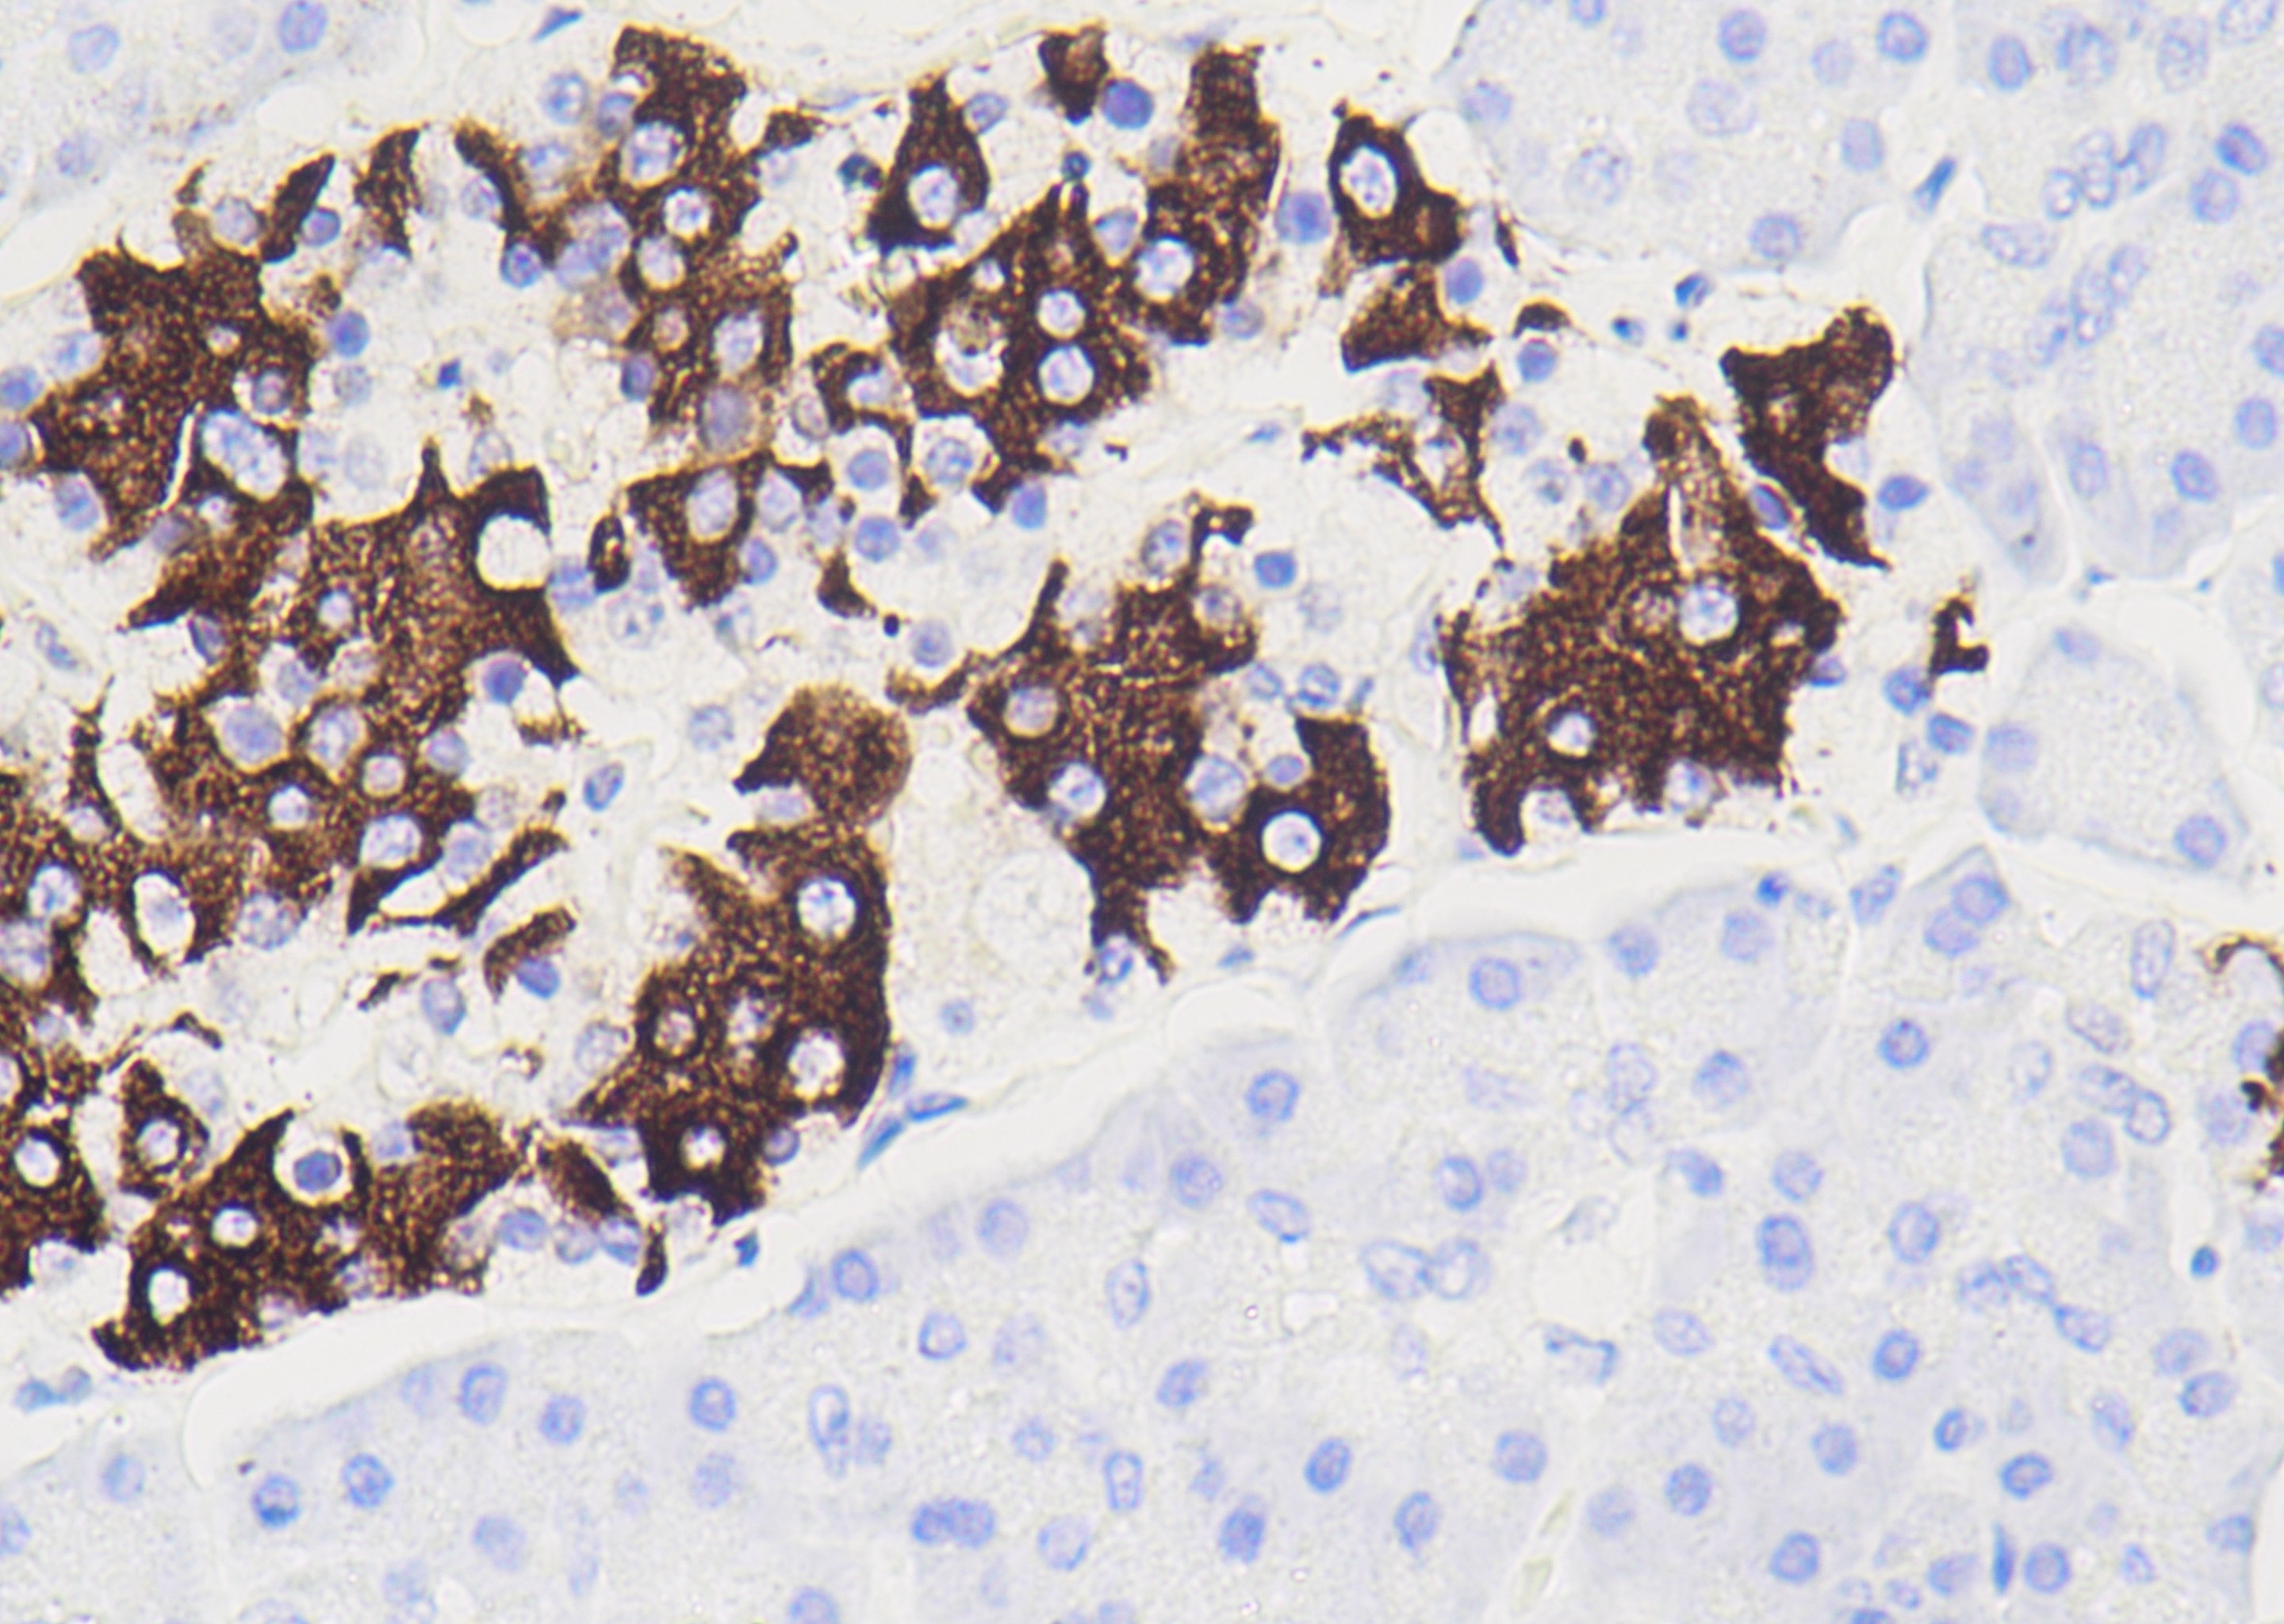

Ki-67

Ki-67是一种与细胞增殖相关的核蛋白,主要用于评估细胞增殖活性。表达模式包括细胞核内颗粒状、斑点状表达,在病理报告中的指数高低与许多肿瘤分化程度、浸润、转移及预后密切相关。Ki-67可用于Burkitt 淋巴瘤的诊断,且与神经内分泌肿瘤分级、滤泡性淋巴瘤与反应性滤泡的鉴别等有关;还可作为多种恶性肿瘤的预后指标。